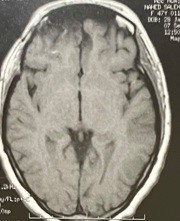

ورم بقاع الجمجمة بالفص الامامي

frontal lobe basement tumor

An image of magnetic resonance imaging with dye on the brain of a meningioma in the anterior chamber at the base of the skull before and after successful microscopic surgery to remove it.